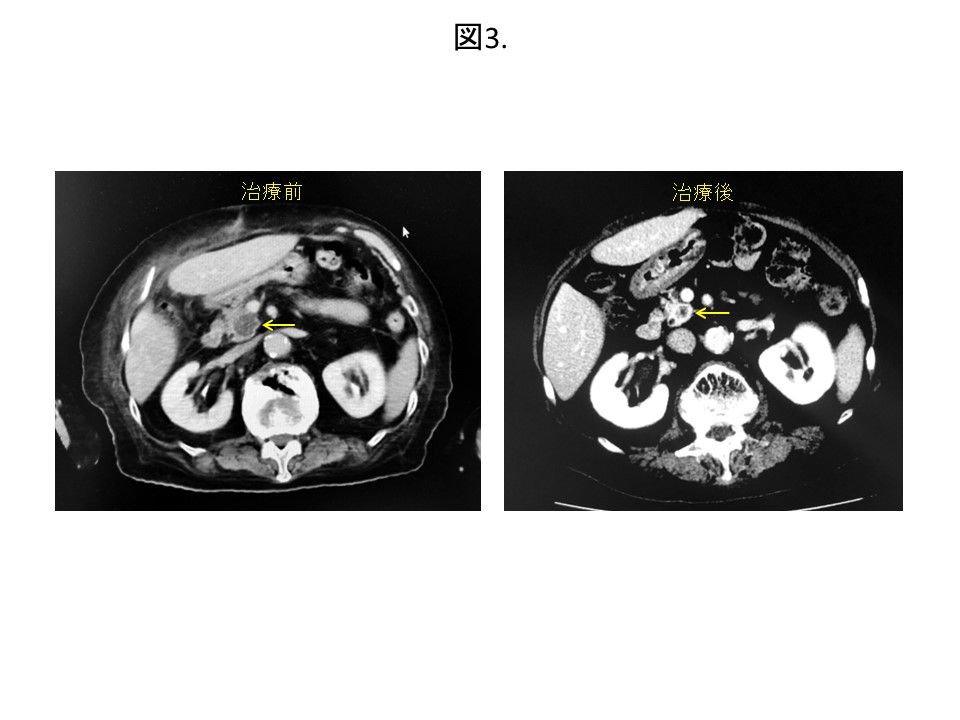

●膵癌85歳女性:ご高齢で手術や抗癌剤治療が困難なため、サイバーナイフで通院治療を行いました。照射後1年半が経過し、癌は小さくなりそのまま大きくなりません。他の場所への転移もなく、とても元気に生活されています(図3)。